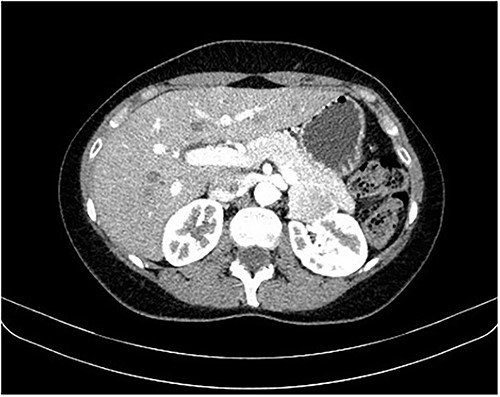

During a screening imaging examination of her liver disease, a lesion suspected of malignancy was detected. The ultrasound disclosed a hypoechoic nodule, vaguely heterogeneous, located in segment VII, subcapsular, and with ~22 mm in diameter (Fig. 1). Liver blood tests and serum alpha-fetoprotein level were normal. For better characterization, a CT scan was performed. The CT showed, in addition to signs of chronic liver disease, the presence of a solid subcapsular nodule of segment VII, measuring 23 mm, with hypervascular behavior in the arterial phase (Fig. 2) and washout in late venous phase (Fig. 3).

CT scan showing, in addition to signs of chronic liver disease, the presence of a solid subcapsular nodule of segment VII, measuring 23 mm, with hypervascular behavior in the arterial phase.